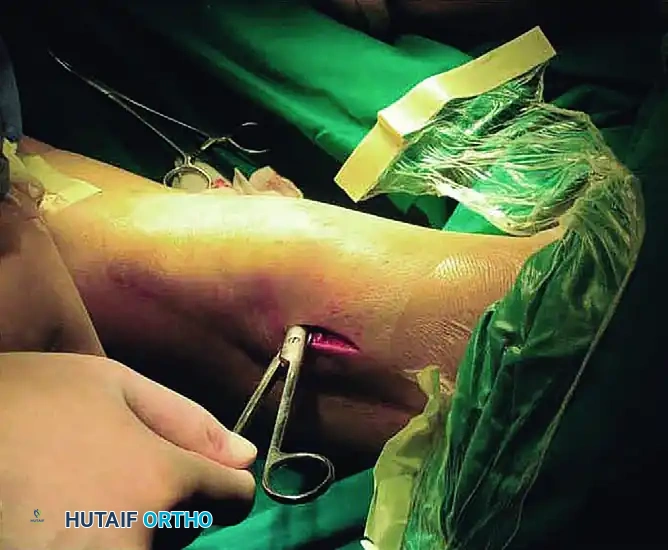

STAGE 2: Mobilization of the Anterior Compartments

- Systematically mobilize the suprapatellar pouch, the patellofemoral compartment, and the anterior interval by sharply dividing the adhesions within these spaces.

- Anatomical Note: The anterior interval is defined as the region of the knee posterior to the infrapatellar fat pad and anterior to the anterosuperior aspect of the tibial plateau. Obliteration of this space is a major contributor to patella infera and restricted flexion.

- Separate the tendinous tissue of the vastus intermedius from the posterior surface of the rectus femoris and the anterior surface of the femur.

STAGE 3: Medial Retinacular Release

- Using a percutaneous inside-out technique, release the medial patellar retinaculum through the suprapatellar pouch, patellofemoral compartment, and anterior interval that were reestablished in Stage 2.

- Pitfall Avoidance: Take extreme care to delineate the medial arthrotomy margin. This margin starts from the medial epicondyle of the femur and slants laterally to the tibial tubercle. You must avoid detachment of the vastus medialis from its critical insertion at the superomedial corner of the patella.

- Free the medial retinaculum from the medial femoral condyle, and free the vastus medialis from the distal third of the femur to fully restore the medial recess.